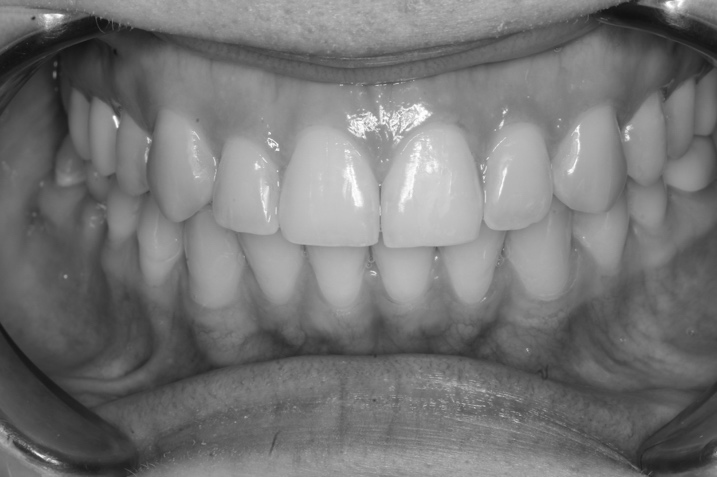

Completion of orthodontic treatment was accompanied by the removal of the bracket system with the installation of retainers on the oral surface of the anterior teeth of the upper and lower jaws, as well as prosthetics with an artificial crown on an implant in the area of the missing 4.6 (Fig. 9).

Fig. 9. Closing of the dental arches after completion of treatment